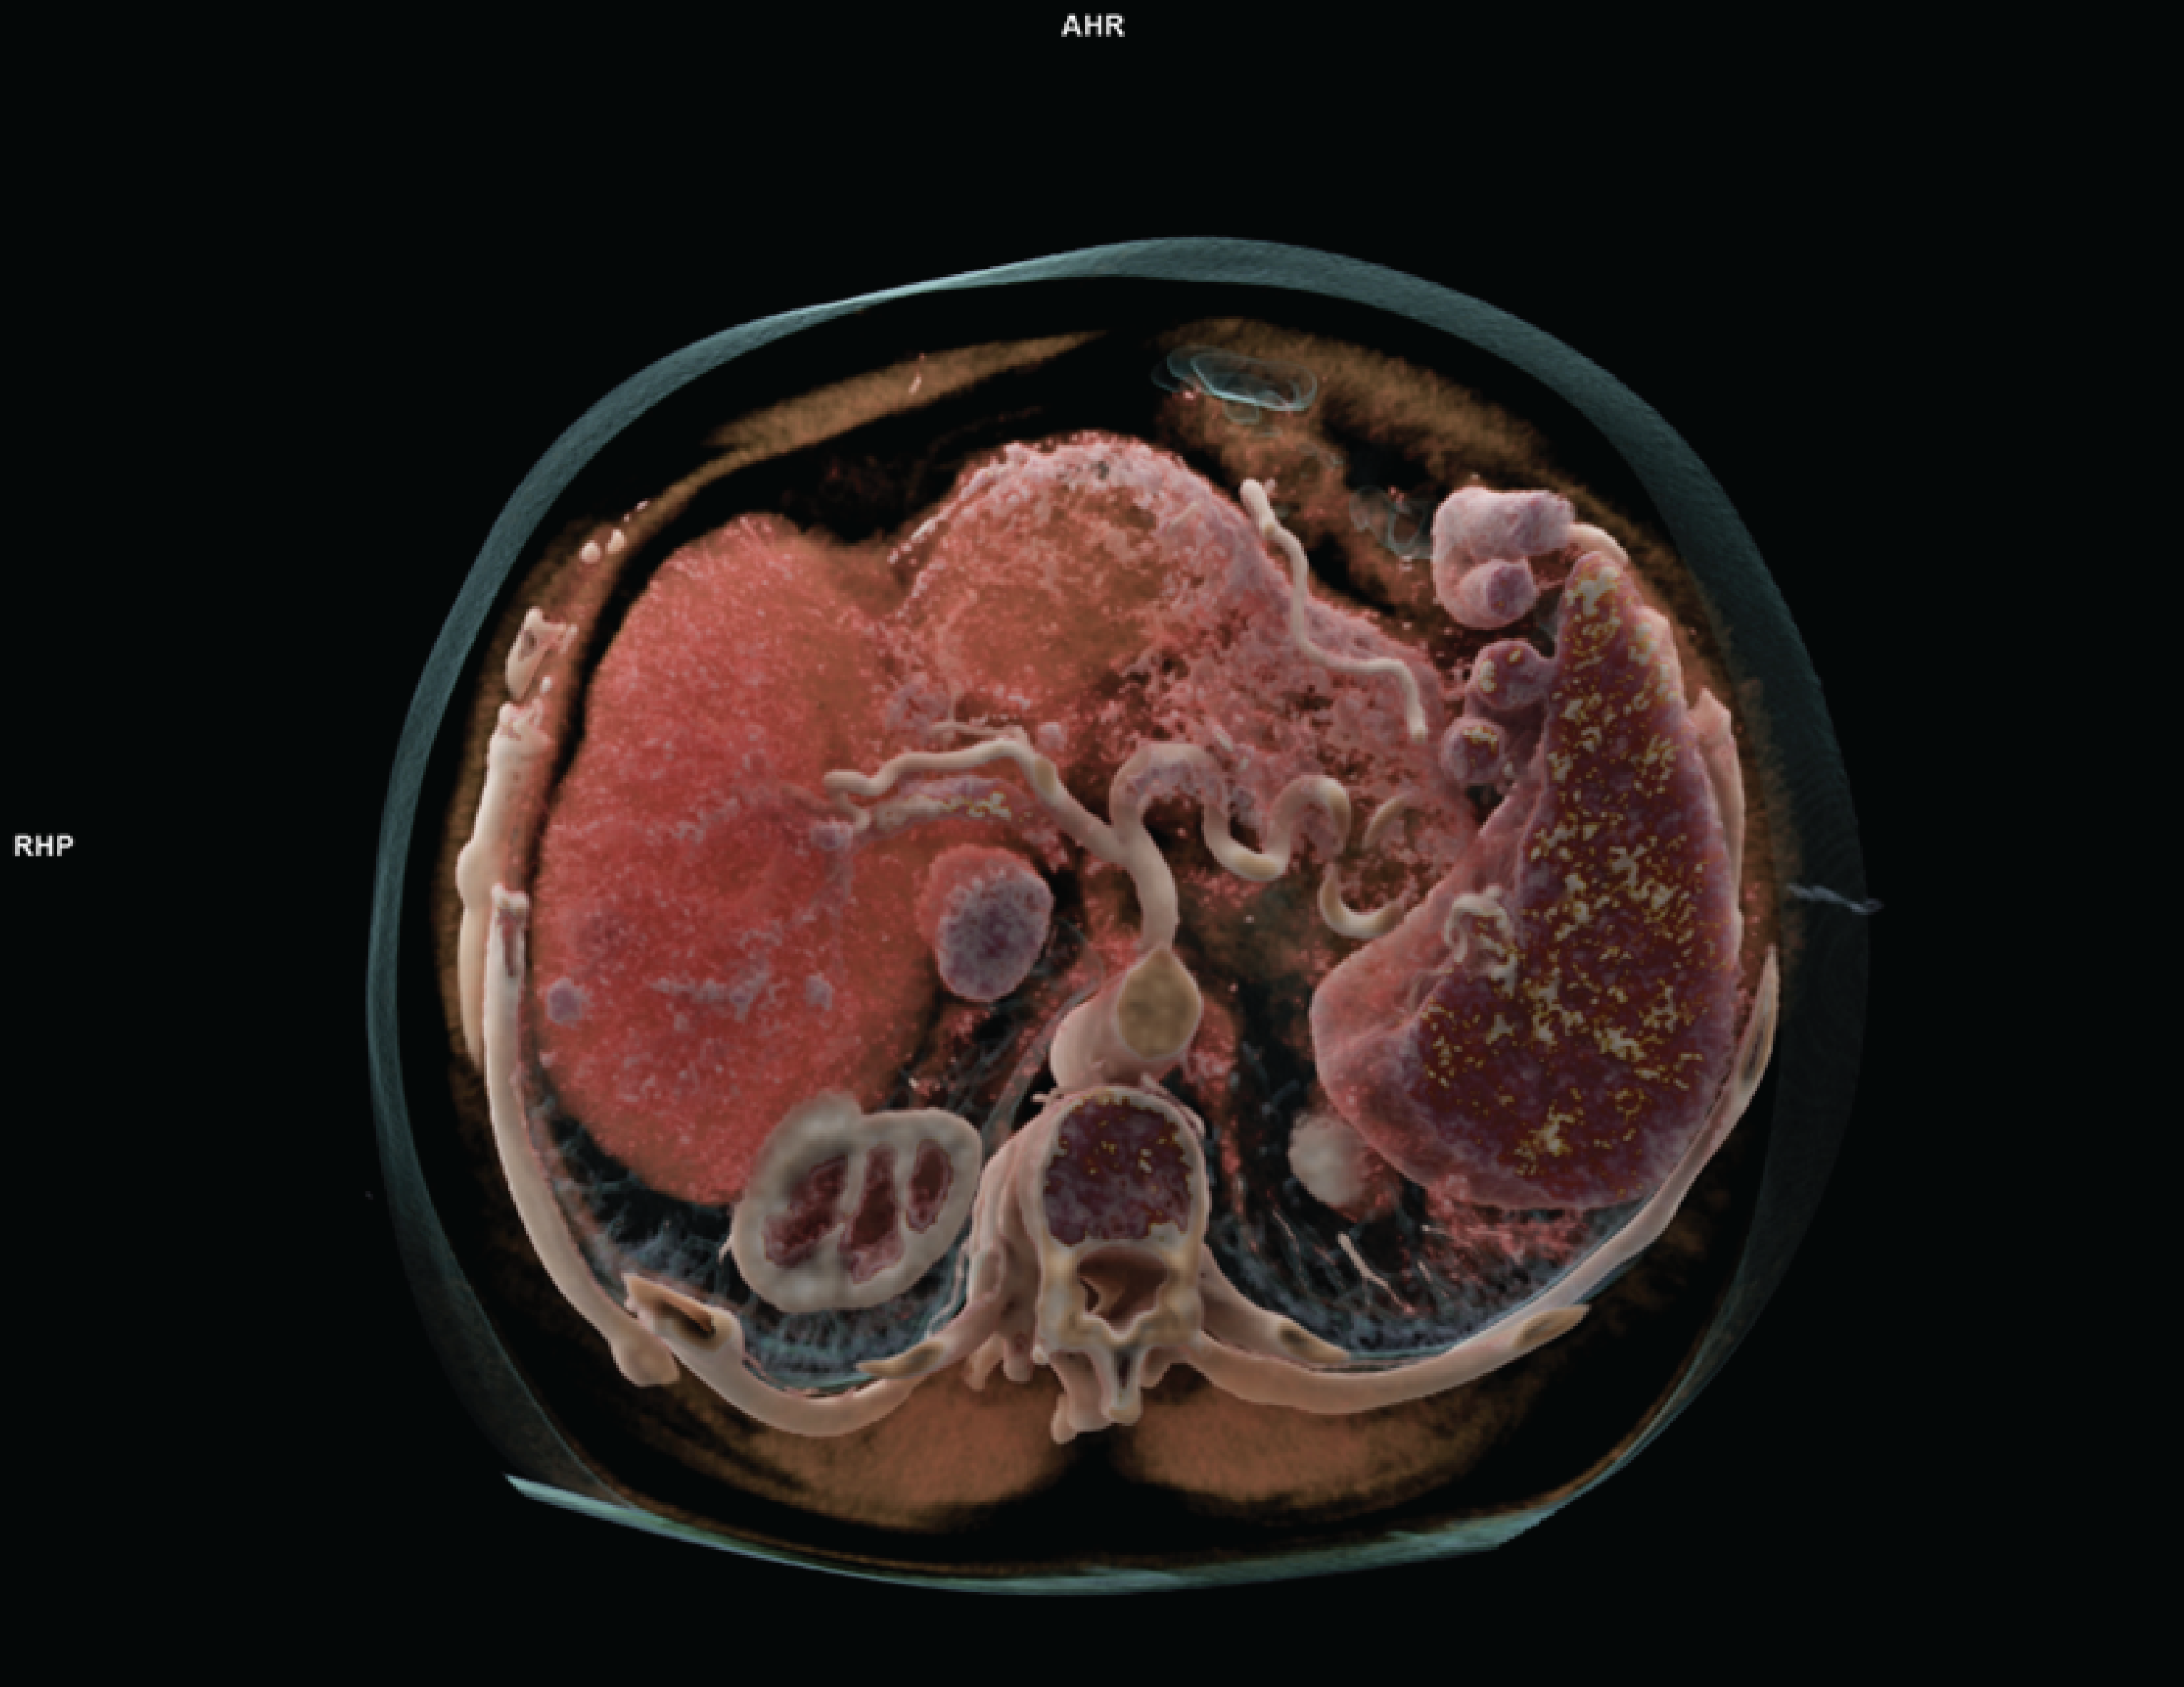

The main components of a CT scanner are an X-ray tube, a gantry (i.e., scanning unit that includes detectors), and a computer.11 Conventional CTs use energy-integrating detectors (EIDs) that rely on scintillators to convert X-ray photons to visible light, and the integrated photon energies are then recorded as electric signals.12 PCCT scanners, also referred to as spectral PCCT, use a novel approach in the way CT systems detect X-rays. PCCT uses a semiconductor material (e.g., cadmium zinc telluride,13,14 silicon15) to directly convert each incident photon into an electrical signal that can be read quickly by the detector circuity to “count” each individual photon.13 When an incident photon strikes the detector, it creates an electric charge cloud in the detector material that is directly proportional to the energy of the incident photon.12,13,16 Based on the measured energy, the counted photons are sorted into energy bins that are used to generate optimal image quality with inherent spectral information using advanced reconstruction techniques, ultimately providing more usable data (Figure 2).3,12,13 Examples of PCCT scanners are presented in Table 1.

Figure 2: Cross-Sectional Output Image From the NAEOTOM Alpha Photon-Counting CT Scanner

Source: Erasmus Medical Center, Rotterdam, NL. Siemens Healthineers.